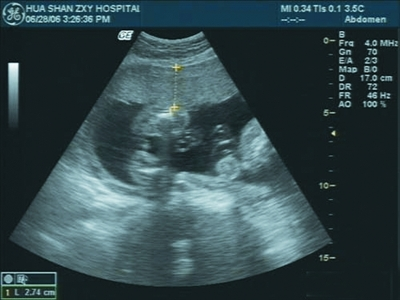

(B超检查影像图)

【B超检查的作用】妇科B超排查范围广,准确性高,是女性做妇科检查必选的项目之一。主要是用于盆腔、附件区域是否存在炎症感染,子宫发育情况,子宫内膜的疾病排查,包括子宫肌瘤,卵巢囊肿,以及对妊娠发育情况的检查。